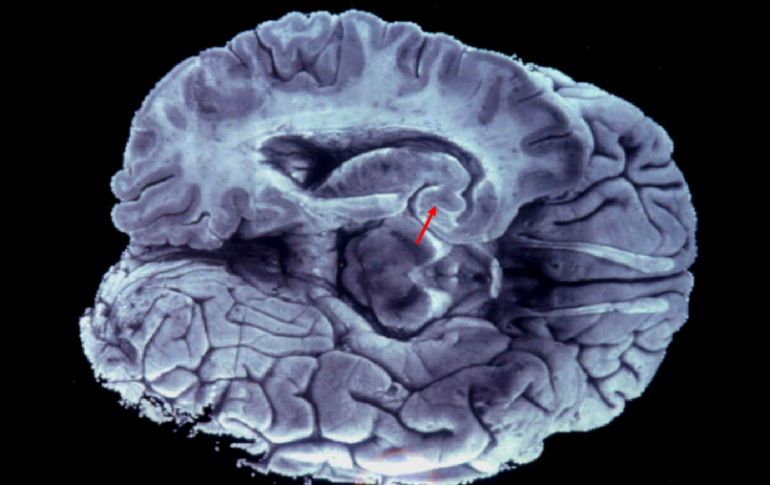

El comunicado refiere que gracias a las imágenes del cerebro obtenidas mediante tomografía computarizada o resonancia magnética, se puede observar la disminución de las neuronas o el desarrollo de proteínas conocidas por favorecer al alzhéimer.